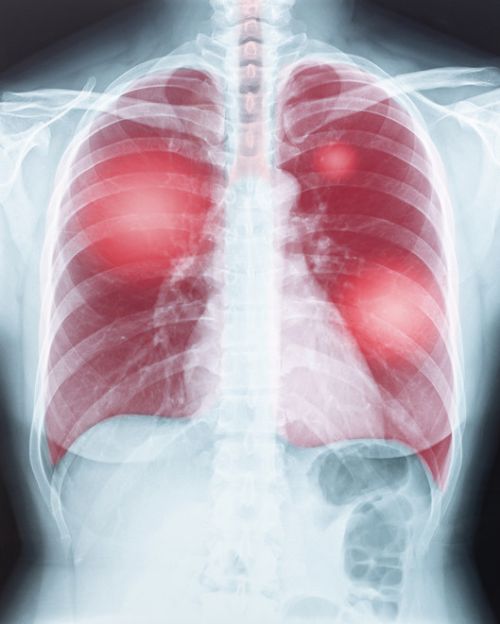

Úmrtiam na zápal pľúc sa da predchádzať očkovaním proti pneumokokovým infekciám

Viac ako 2 500 ľudí ročne na Slovensku zomrie na následky sezónnych respiračných infekcií. Ide predovšetkým o ľudí nad 65 rokov a chronicky chorých pacientov. Seniorov ohrozuje aj pneumokokový zápal pľúc, pred ktorým je možné sa efektívne brániť. Odborníci odporúčajú ako najúčinnejšiu prevenciu očkovanie. Pre klientov zariadení sociálnych služieb je povinné. Očkovanie nie je viazané na ročné obdobie a vakcína môže byť podaná kedykoľvek počas celého roka.

Baktéria Streptococcus pneumoniae sa prenáša kvapôčkovou infekciou a môže spôsobiť život ohrozujúce invazívne ochorenia, ako je meningitída, sepsa alebo pneumokokový zápal pľúc.

Ochorenia dýchacej sústavy sú treťou najčastejšou príčinou úmrtí, hneď po kardiovaskulárnych a onkologických ochoreniach. „Stopercentná zaočkovanosť cieľovej populácie dospelých na Slovensku proti pneumokokom by podľa výpočtov zabránila 4 500 prípadom pneumokokového zápalu pľúc a z toho 600 úmrtiam ročne. Zápal pľúc spôsobený baktériou Streptococcus pneumoniae je vážne ochorenie, ktoré môže byť život ohrozujúce, a liečba je náročná. Najviac prípadov ochorenia sa vyskytuje v zime, čo je spôsobené zníženou obranyschopnosťou organizmu, zvýšeným výskytom chorôb dýchacieho ústrojenstva a rýchlym a ľahkým prenosom baktérií kvapôčkami. Inkubačná doba – čas od nákazy po vypuknutie prvých príznakov – sa odhaduje na 1 až 3 dni. Ide o infekčné ochorenie, znamená to, že nie je možné dostať zápal pľúc len z prechladnutia,“ povedala MUDr. Katarína Dostálová, pneumologička, Bratislava.